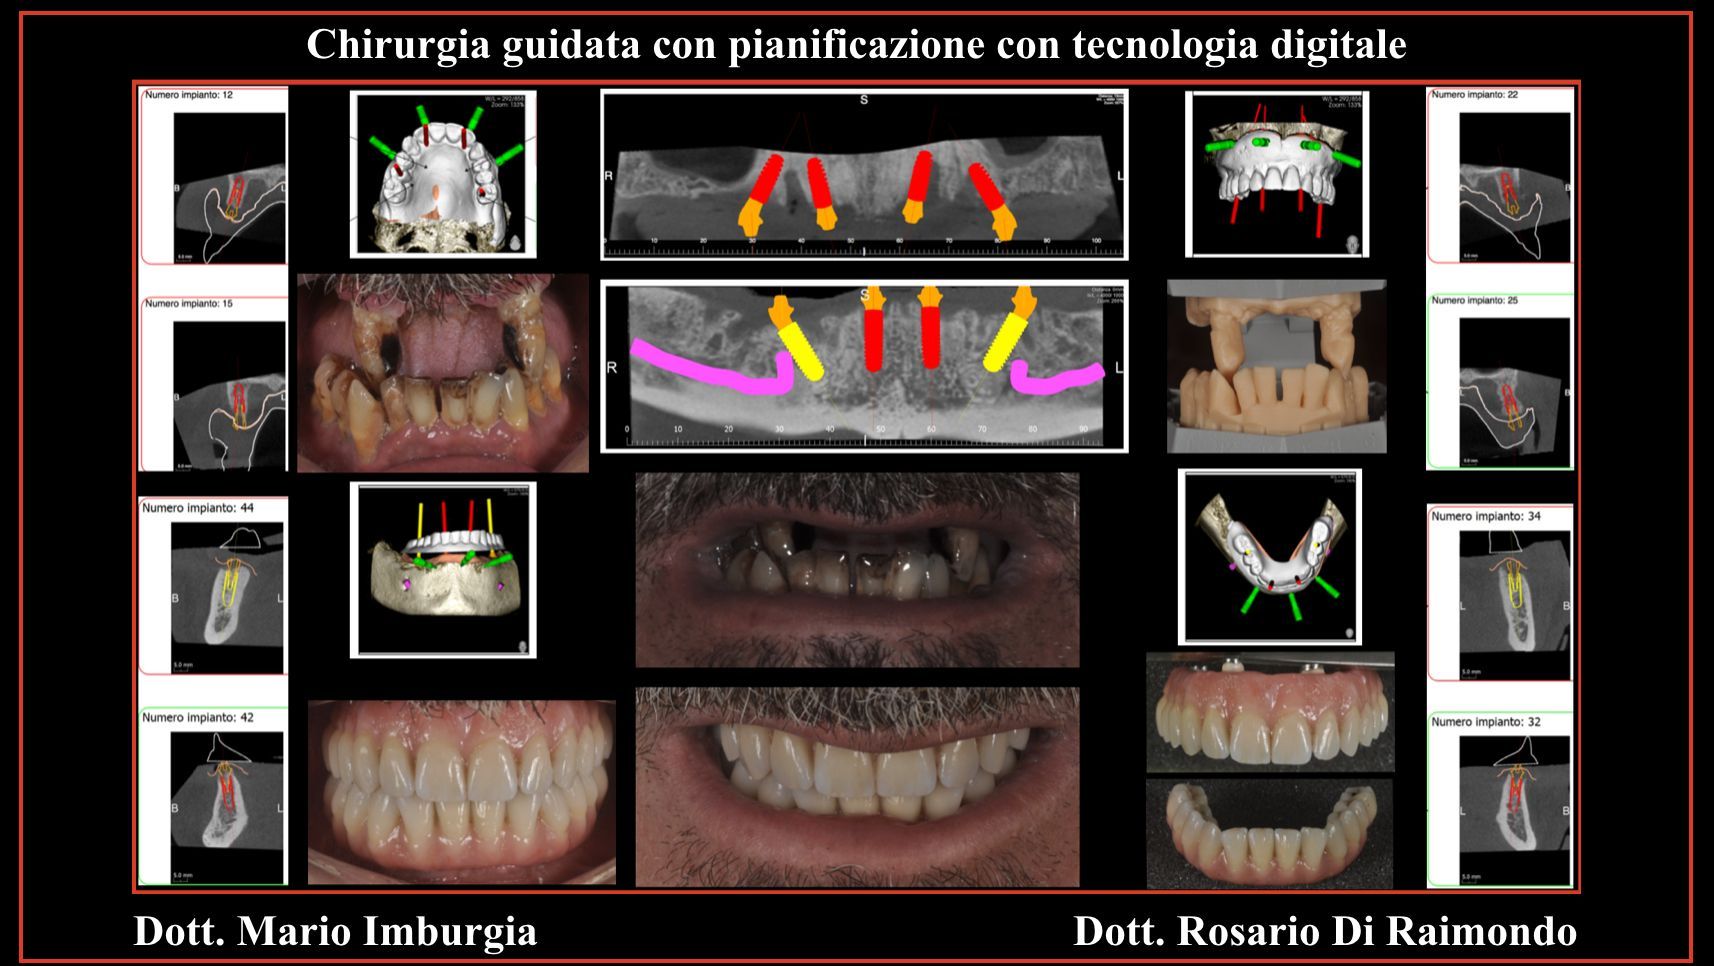

Quando parliamo di chirurgia guidata o implantologia guidata, facciamo riferimento a tecniche “flapless”, quindi minimamente invasive, nelle quali attraverso le nuove tecnologie di pianificazione chirurgica, associando i dati dell'impronta digitale del paziente con le corrispondenti sezioni della radiologia 3D (TAC o CBCT), è possibile non solo programmare con estrema precisione gli interventi chirurgici, ma anche ridurre se non addirittura eliminare i disagi intraoperatori e post-chirurgici per il paziente che non ha nessuna limitazione funzionale nei giorni successivi.

Casi Trattati

Di seguito riportiamo alcune fotografie di casi di Implantologia già trattati.